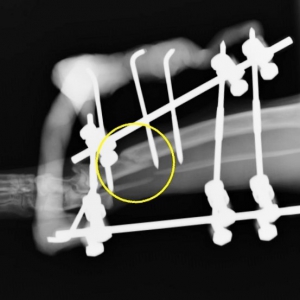

下の写真は骨折の整復手術の開始から2時間超、骨折端の位置決めが終わって、手術もそろそろ佳境に差し掛かった時点での写真です。

レントゲン写真は、レジンでの補強後の最終的なものです。骨折直後の写真と比べてると、大きくずれていた骨折部位がほぼ戻っているのがおわかりになるでしょうか?